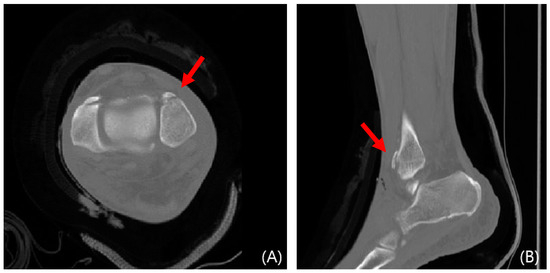

This study evaluated syndesmosis reduction by analyzing postoperative axial CT images captured 1 cm proximal to the tibial plafond (Table 1 and Figure 1) [16,17,18,19]. Four radiographic measurements were chosen and assessed with a PACS image viewer software (Dejaview2 version 1.0, Dongwun Information Technology, Republic of Korea). Two independent observers, blinded to patients’ clinical outcomes and current complaints, objectively evaluated the measurements. The process was repeated after a 6-week interval to ensure reliability.

In cases of instability, a mini-plate (Arix Hand System, Jeil Medical, Seoul, Republic of Korea) is shaped to cover the Wagstaffe fracture and secured using 2.0 mm cortical screws and locking screws (Figure 3). For smaller fractures, screws were applied to the proximal and distal sections of the mini-plate at the fracture site. Screw fixation was performed at the fracture site when possible (Figure 4). Subsequently, tibiofibular joint stability was assessed through arthroscopy. Figure 5 and Figure 6 show the preoperative plain X-ray and CT images of a 47-year-old female with a Wagstaffe fracture. Figure 7 shows the postoperative plain X-ray image of a Wagstaffe fracture treated with open reduction and internal fixation using the described technique. Postoperative CT images were used to further confirm the reduction and fixation (Figure 8).

Figure 6. Preoperative CT images of a 47-year-old female with a Wagstaffe fracture (red arrow). Axial (A) and sagittal (B) views.